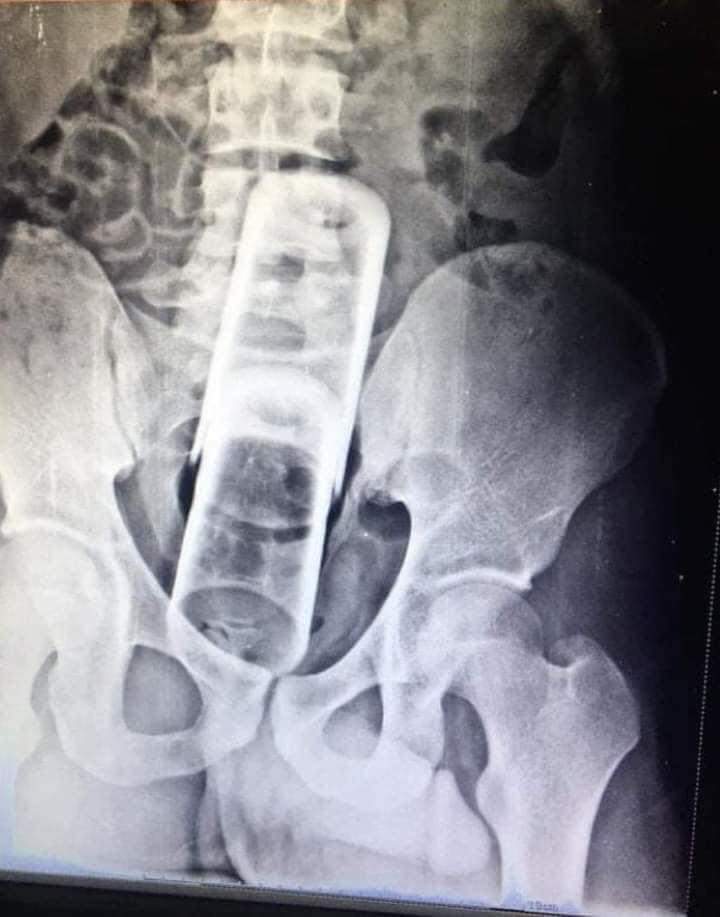

حوادث:"مصر"بالصور استخراج كوبين زجاجيين أحدهما مكسور من أمعاء(شاب)

واقعة غريبة:استخراج كوبين زجاجيين أحدهما مكسور من أمعاء وقولون شاب في مستشفى بالمنصورة شمال مصر